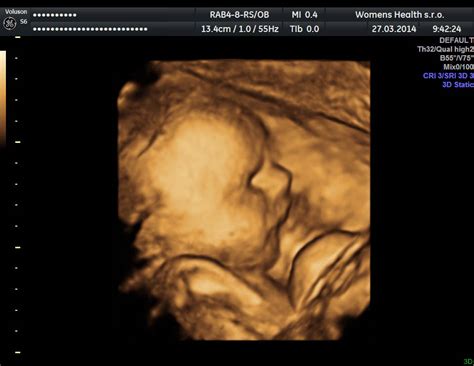

3D a 4D ultrazvuk

3D ultrazvuk je ultrasonografická metóda zobrazenia plodu trojrozmerným (trojdimenzionálnym) spôsobom. 3D ultrazvuk zobrazuje síce priestorový, ale iba statický (nepohyblivý) obraz plodu. 4D ultrazvuk je o úroveň vyššie, čiže zobrazovanie plodu je v “štyroch” dimenziách, tzn. 3D ultrazvukové zobrazenie plodu, ale nie statické, ale pohyblivé zobrazenie v čase. To je v zásade to “štvrté D - 4D”. Pri 3D ultrazvuku vytvoríme obrázok skutočného vzhľadu Vášho bábätka a pri 4D ultrazvuku naviac uvidíte ako sa v danom okamihu bábätko pohybuje. To ako dobre bude možnosť si prehliadnuť bábätko záleží vždy od jeho spolupráce a od množstva plodovej vody.

Ideálna doba na vyšetrenie je medzi 12. - 14. týždňom a 20. - 28. týždňom tehotenstva.